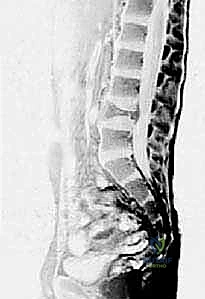

- أعراض عصبية: إذا نشأ الكيس في العمود الفقري، فقد يضغط على الحبل الشوكي أو الأعصاب، مما يسبب تنميلاً، ضعفاً في الأطراف، أو حتى شللاً في الحالات المتأخرة.

صورة الرنين المغناطيسي (MRI) توضح بوضوح السائل المتجانس داخل كيس العظم أحادي الغرفة، مما يساعد الأستاذ الدكتور محمد هطيف في استبعاد الأورام الصلبة.

التصوير بالرنين المغناطيسي (MRI):

- ضروري لتقييم محتوى الكيس وتأثيره على الأنسجة الرخوة المحيطة وصفيحة النمو.

في الـ ABC، يُظهر الرنين المغناطيسي علامة كلاسيكية تُعرف بـ "مستويات السائل-السائل" (Fluid-Fluid Levels)، والتي تنتج عن ترسب خلايا الدم الحمراء وانفصالها عن مصل الدم داخل تجاويف الكيس.